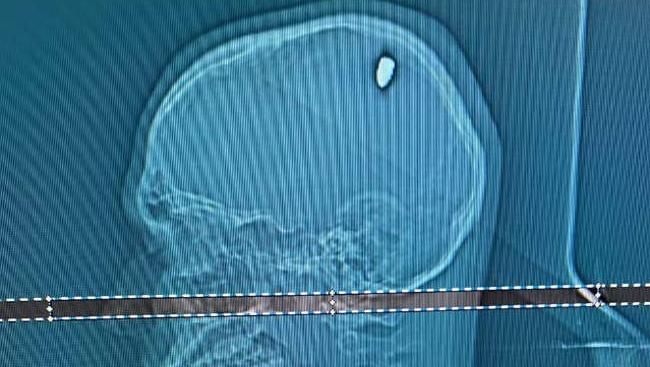

Seorang pria berpesta selama 4 hari setelah tertembak di kepalanya. Foto: Tangkapan layar Oddity Central

Lantaran khawatir dengan kondisinya, Mateus langsung pergi ke rumah sakit setempat untuk memeriksakan diri. Berdasarkan hasil pemeriksaan CT scan, dokter menemukan bahwa ada peluru 9mm yang bersarang di kepalanya, yang awalnya dikira hanyalah lemparan batu saja.

Dokter kemudian langsung merencanakan operasi pengangkatan peluru dari otak Mateus. Meskipun ada risiko yang terkait dengan prosedur tersebut, tetapi operasi itu telah berhasil dilakukan, dan Mateus kini sedang dalam tahap pemulihan.